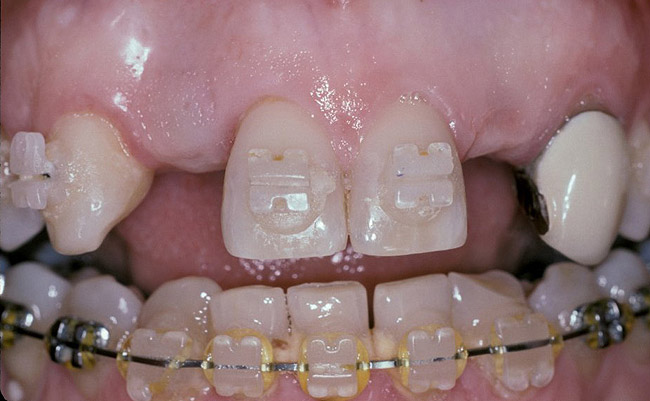

Figure 7   Completion of maxillary orthodontic treatment created adequate space for implants at site Nos. 7 and 10. The retained right primary maxillary canine was extracted and orthodontic movement was performed to translate the right permanent canine into the No. 6 position, creating room for a No. 7 implant, and generally align the teeth.

Figure 7